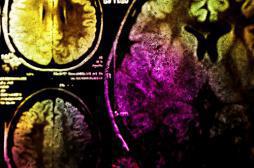

Neuropeptide

LES MALADIES

SYMPTÔMES